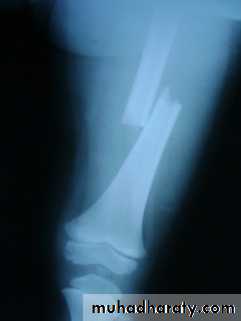

Femoral shaft fracture

Surgery – orthopedic – 5th stage – Dr. hishamThis fracture occurs at any age, it is common especially in young adults, and usually results from a high energy injury, such as

( car accident , fall from height).

X-ray :

Shows the type of fractures, and displacement. The x-ray should include the hip and knee and x-ray of pelvis to avoid missing segmental fractures, knee injuries, fractures of neck of femur, dislocation of hip, fractures of acetabulum and pelvis.